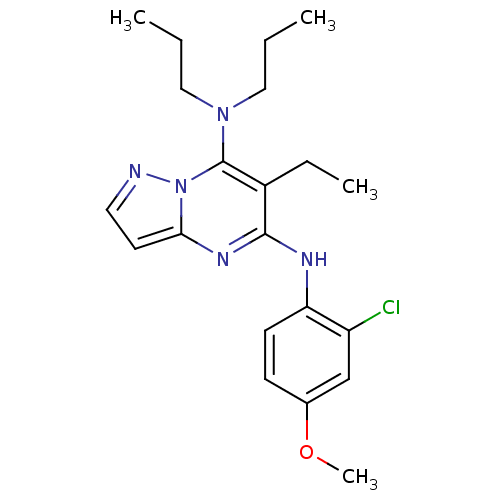

TargetCorticotropin-releasing factor receptor 1(Homo sapiens (Human))

Dupont Pharmaceuticals

Curated by ChEMBL

Dupont Pharmaceuticals

Curated by ChEMBL

Affinity DataEC50: 0.220nMAssay Description:Activity of peptidic agonists on corticotropin releasing factor receptor receptor using agonist-stimulated adenylate cyclase assayMore data for this Ligand-Target Pair

TargetCorticotropin-releasing factor receptor 1(Homo sapiens (Human))

Dupont Pharmaceuticals

Curated by ChEMBL

Dupont Pharmaceuticals

Curated by ChEMBL

Affinity DataEC50: 0.300nMAssay Description:Antagonist activity at human CRF1 receptor expressed in CHO-K1 cells assessed as CRF-stimulated cAMP accumulation by enzyme immunoassayMore data for this Ligand-Target Pair

Affinity DataEC50: 0.420nMAssay Description:Antagonist activity at CRF-R1 in mouse AtT-20 cells assessed as inhibition of human CRF induced cAMP accumulation after 30 mins by radioimmunoassayMore data for this Ligand-Target Pair

Affinity DataEC50: 0.440nMAssay Description:Antagonist activity at CRF-R1 in mouse AtT-20 cells assessed as inhibition of human CRF induced cAMP accumulation after 30 mins by radioimmunoassayMore data for this Ligand-Target Pair

Affinity DataEC50: 0.450nMAssay Description:Antagonist activity at CRF-R1 in mouse AtT-20 cells assessed as inhibition of human CRF induced cAMP accumulation after 30 mins by radioimmunoassayMore data for this Ligand-Target Pair